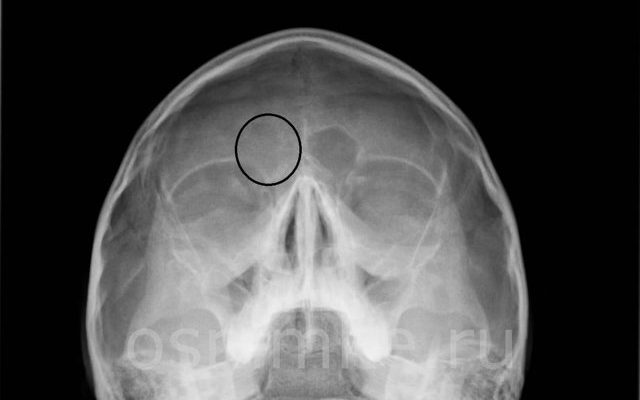

Заболевание отображается затемнением с верхней горизонтальной отметкой.

Фронтит на рентгеновском снимке в прямой проекции с фокусировкой на лобной области выглядит следующим образом:

- форма и состояние лобных пазух;

- наличие воспалительной реакции;

- количество экссудата;

- потемнение в кистозных массах;

- уменьшение воздушной полости в носовых пазухах;

- степень распространения;

- смещение отдельных стен или их фрагментов.

При опухолях, особенно кистах, на изображении видны круговые затемнения (белые пятна), содержащие жидкость.

Снижение плотности воздуха (пневматизация) происходит в результате скопления секрета в верхней горизонтальной области. При изменении положения тела, например поворотом головы, инфильтрат смещается.